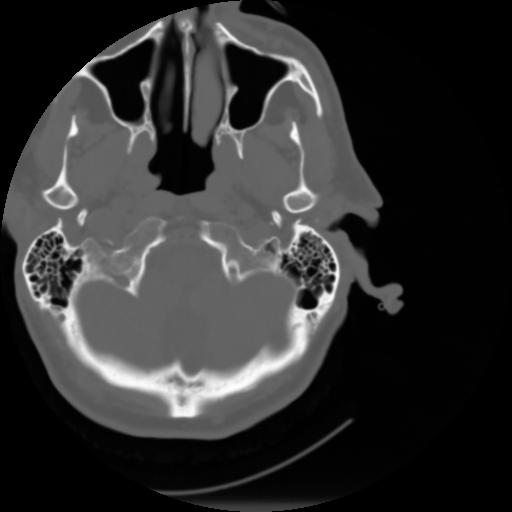

3 CEREBRO,,Axial,3.0,CEREBRO,,